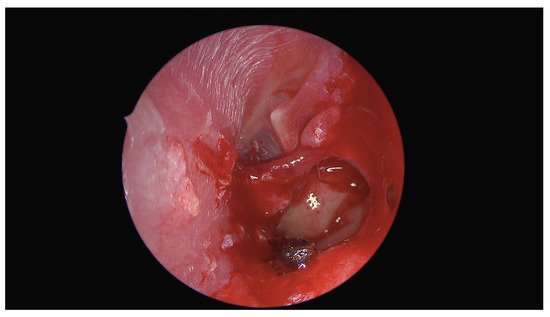

Unusual Foreign Body in the Middle Ear: Surgical Removal of a Live Ant Entering the Tympanic Cavity Through an Ear Drum Perforation

Kiss, P.; Pock, J.; Habenbacher, M.; Maitz, E.; Lang, A.; Walla, K.; Andrianakis, A. Unusual Foreign Body in the Middle Ear: Surgical Removal of a Live Ant Entering the Tympanic Cavity Through an Ear Drum Perforation. Diagnostics 2024, 14, 2530. https://doi.org/10.3390/diagnostics14222530